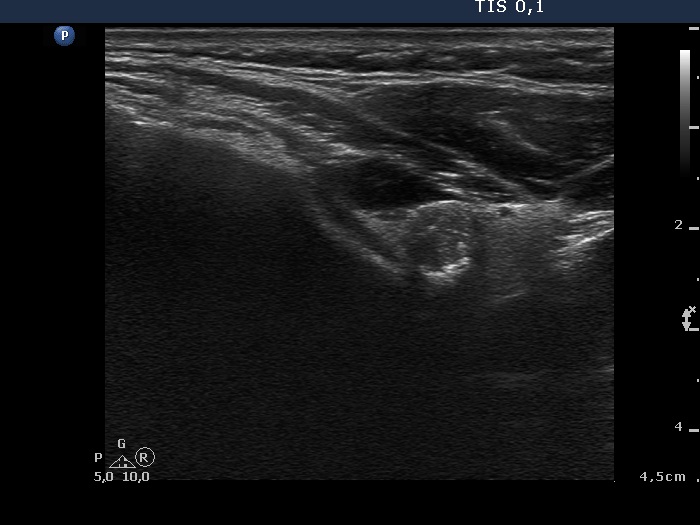

Benign hyperplastic nodule (histological diagnosis) - case 489 |

The nodule had an eggshell calcification.